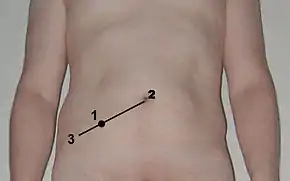

The presentation of acute appendicitis includes acute abdominal pain, nausea, vomiting, and fever. As the appendix becomes more swollen and inflamed, it begins to irritate the adjoining abdominal wall. This leads the pain to localize at the right lower quadrant. This classic migration of pain may not appear in children under three years. This pain can be elicited through signs, which can feel sharp. Pain from appendicitis may begin as dull pain around the navel. After several hours, the pain usually migrates towards the right lower quadrant, where it becomes localized. Symptoms include localized findings in the right iliac fossa. The abdominal wall becomes very sensitive to gentle pressure (palpation). There is pain in the sudden release of deep tension in the lower abdomen (Blumberg's sign). If the appendix is retrocecal (localized behind the cecum), even deep pressure in the right lower quadrant may fail to elicit tenderness (silent appendix). This is because the cecum, distended with gas, protects the inflamed appendix from pressure. Similarly, if the appendix lies entirely within the pelvis, there is typically a complete absence of abdominal rigidity. In such cases, a digital rectal examination elicits tenderness in the rectovesical pouch. Coughing causes point tenderness in this area (McBurney's point), called Dunphy's sign.